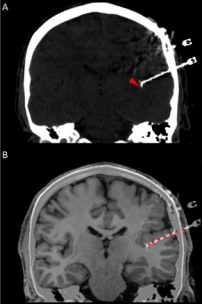

In addition to the very valuable iEEG recordings from the clinical macroelectrodes, our iEEG recordings also include signals recorded with microelectrodes. The additional microelectrodes have a diameter of about 40 μm (smaller than the hair) and spread out of the tip of the clinical intracranial electrode. They are added solely for research purposes and, because of their small size, they can record the electrophysiological firing activity generated by nearby individual neurons. We analyze this data by using algorithms which classify the different waveforms recorded by a single microwire into action potentials generated by different neurons. We also use population decoding methods to extract the information associated by the neurons (e.g. “concept” neurons which preferably fire in response to specific images of the same individual). To localize the site of the macro- and micro-electrodes with high spatial resolution, we combine post-implantation CT scans with pre-implantation neuroimaging scans from the 7-Tesla MRI, available at the University of Magdeburg.

2. © Greene et al., 2021. Reproduced according to the terms of Creative Commons Attribution License. Greene, Patrick, Adam Li, Jorge González-Martínez, and Sridevi V. Sarma. 2021. “Classification of Stereo-EEG Contacts in White Matter vs. Gray Matter Using Recorded Activity.” Frontiers in Neurology 11 (January). https://doi.org/10.3389/fneur.2020.605696.

4. © Carlson et al., 2018. Reproduced according to the terms of Creative Commons Attribution License. Carlson, April A., Ueli Rutishauser, and Adam N. Mamelak. 2018. “Safety and Utility of Hybrid Depth Electrodes for Seizure Localization and Single-Unit Neuronal Recording.” Stereotactic and Functional Neurosurgery 96 (5): 311–19. https://doi.org/10.1159/000493548.